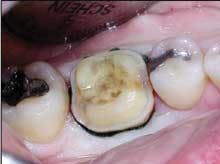

Consider the mush and recurring decay you often find under unbonded amalgams, plus the fractures under weakened cusps or brazenly dead center in sub-amalgam tooth structures. (This is common in baby boomers when canine guidance has been lost.) When I remove an old, defective, amalgam restoration, I recall turning over a rock embedded in the earth and half looking away for fear of finding something scary. Use that simile when recommending replacement of old alloys. It will help you explain the situation (Figures 3 and 4).

When replacing an amalgam that's beginning to fail, you're likely to remove secondary caries and reseal - or in most cases, seal for the first time - the cavo-margin surfaces. You'll often provide shelter and strength for weakened tooth structures by shoeing areas with composite or placing indirect restorations such as crowns or onlays (Figures 5-8).